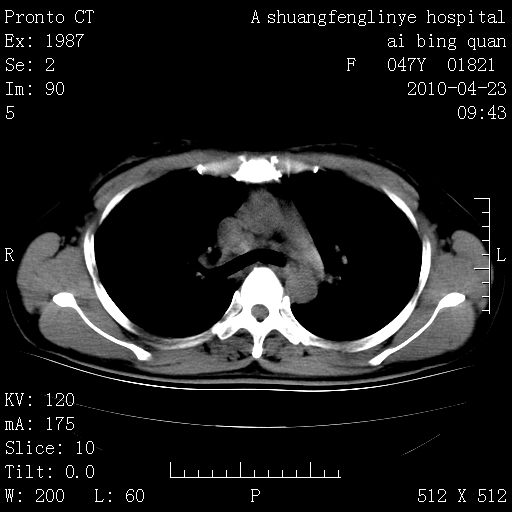

标题: CT25944:胸痛、气短、前几日高烧!肺Ca?请会诊! [打印本页]

标题: CT25944:胸痛、气短、前几日高烧!肺Ca?请会诊!

双肺多发结节,考虑转移瘤,肺癌肺转移不除外

周围型肺癌并肺转移

双肺多发结节,部分密度较高,最大结节边缘光滑。临床有“胸痛、气短、前几日高烧”病史。首选考虑:右肺感染性病变!建议积极消炎后复查!